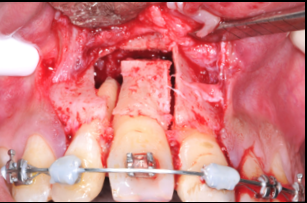

The management of the anterior open bite may be quite challenging and in some cases necessitates a multidisciplinary approach. We present here a patient suffering from an anterior open bite with an ankylosed central incisor due to previous trauma. The anterior open bite was corrected using conventional orthodontics and the ankylosed incisor was repositioned in the correct tri dimensional position using segmental osteotomy. The repositioned bone block needed 5 months of stabilization and the prosthetic rehabilitation of the anterior maxilla was completed using e-max crowns. At 24 months ,the result was stable with no relapse and an excellent pink and white esthetic score.